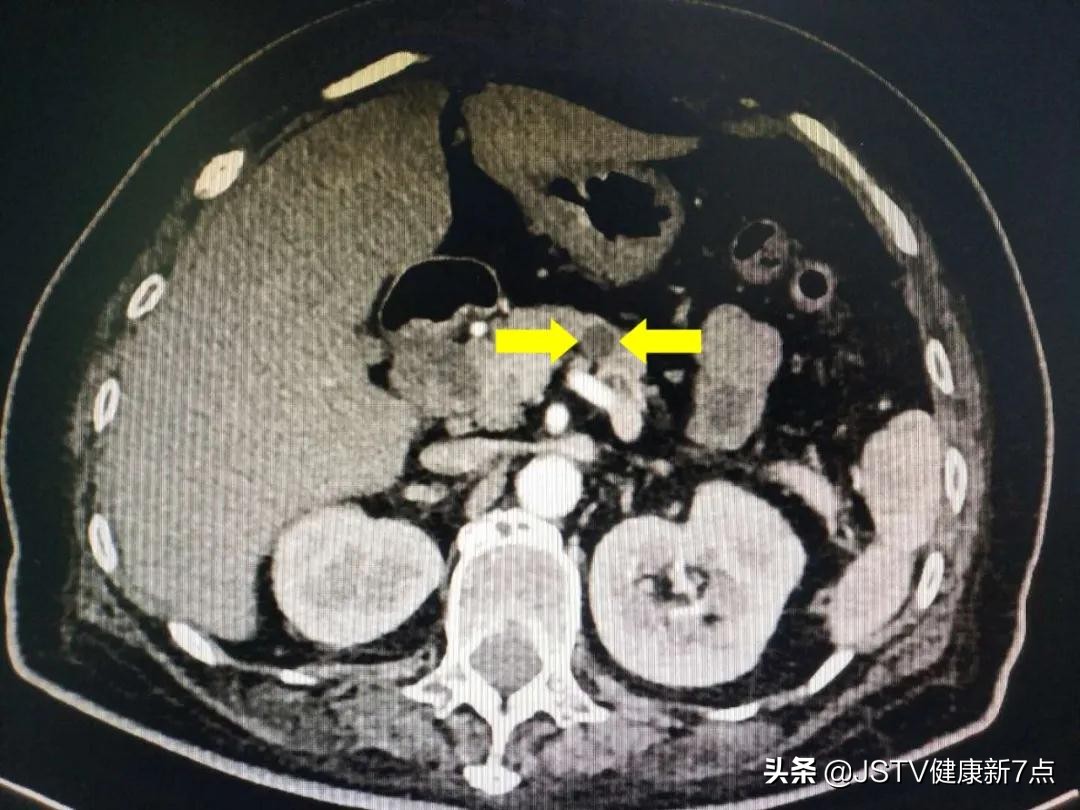

钱教授自有推断。结果一检查,竟然发现了在李先生胰腺尾部有一个可疑的肿块!

黄色箭头指出胰腺肿块的位置

进一步检查,竟然是胰腺癌,但是幸运的是肿瘤不算太大,也没有侵袭到其他部位。